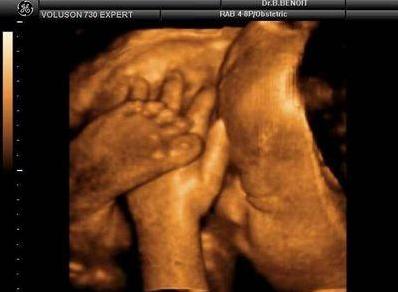

【在妇产科医院,你可以看到这样的胎宝】

麻麻,我在咬手指哟!

霍霍,打拳啦~